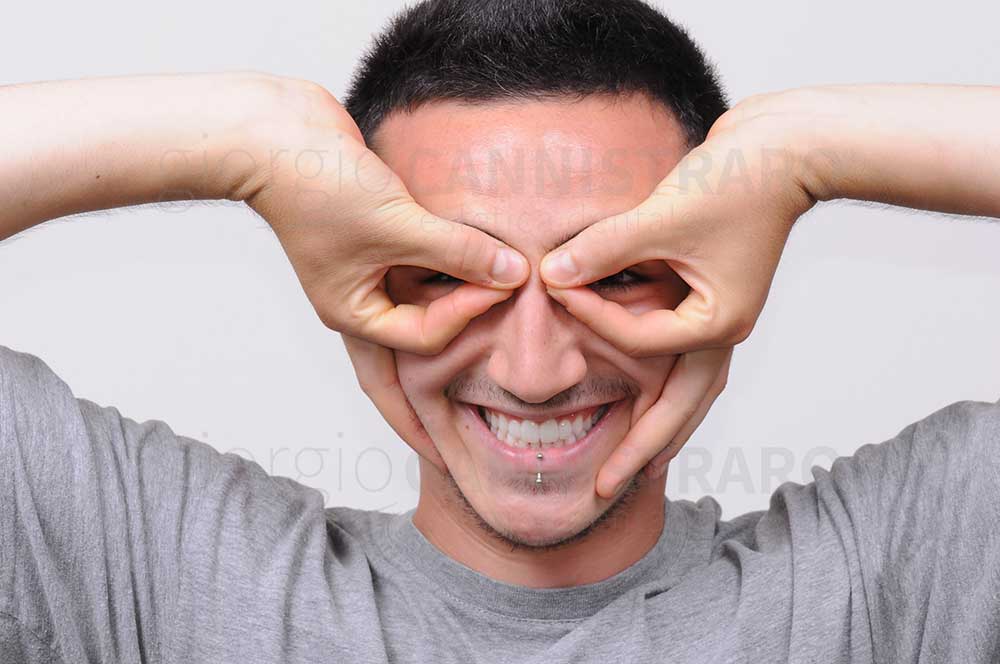

Ragazzo 30 anni